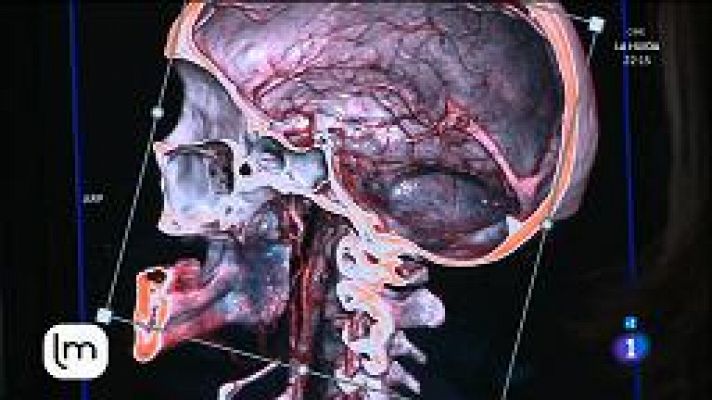

Consejos para cuidar nuestro cerebro

Consejos para cuidar nuestro cerebro